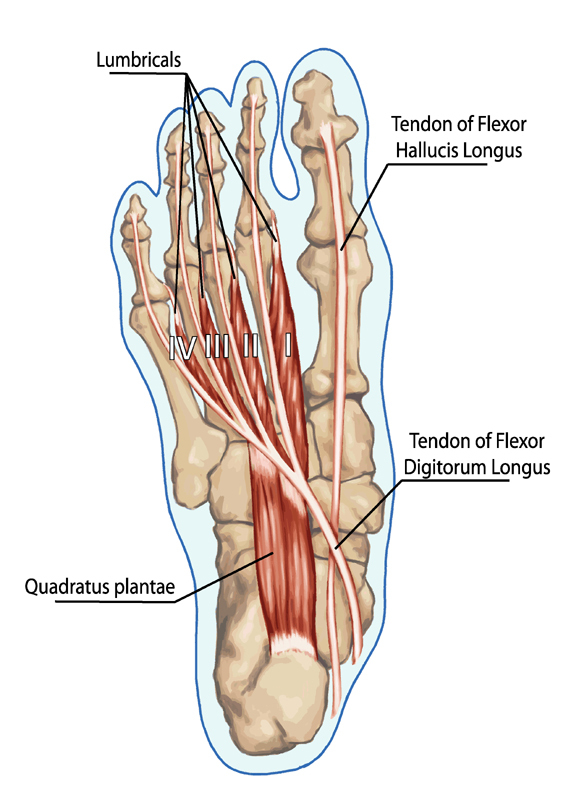

Anatomy Nugget: Why the Feet Are So Important

The feet contain over 7,000 nerve endings and a huge number of mechanoreceptors — tiny sensory structures that detect pressure, vibration and movement.

This is called proprioception, and it is one of the reasons stimulation of the feet can influence relaxation, posture and stability.